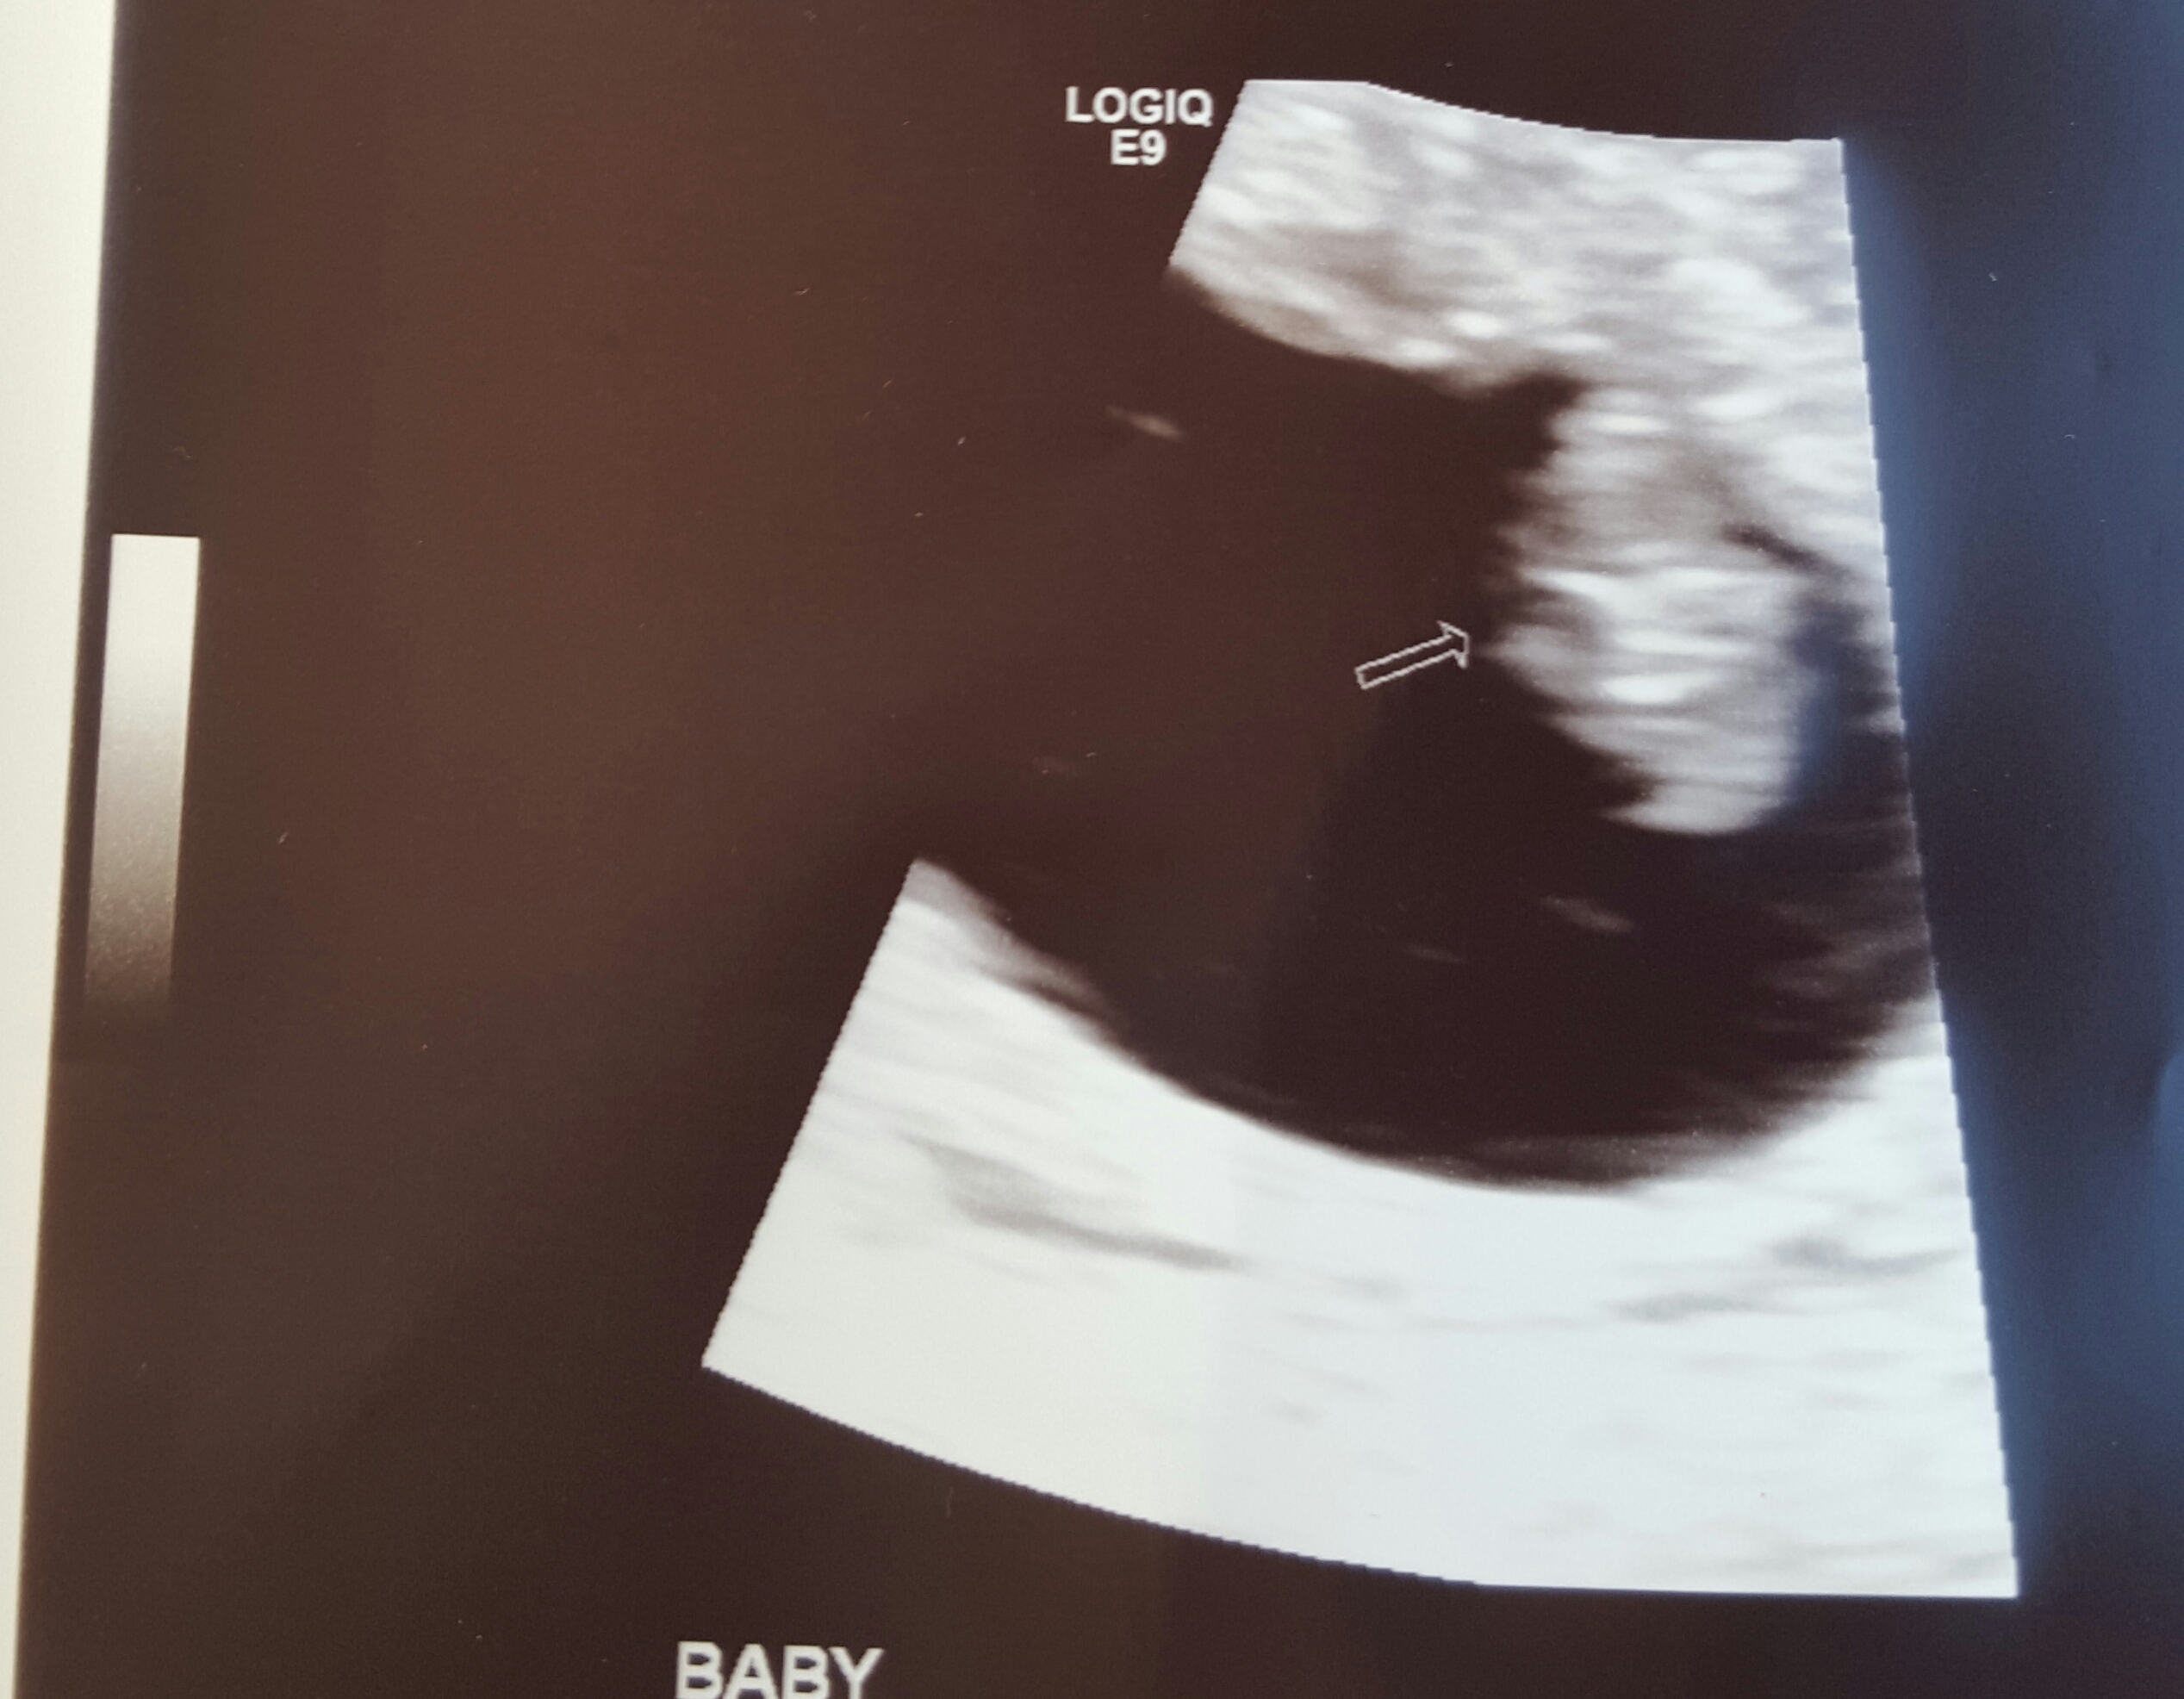

I am due June 5th. Hr was 160

It was so amazing! My miracle baby.